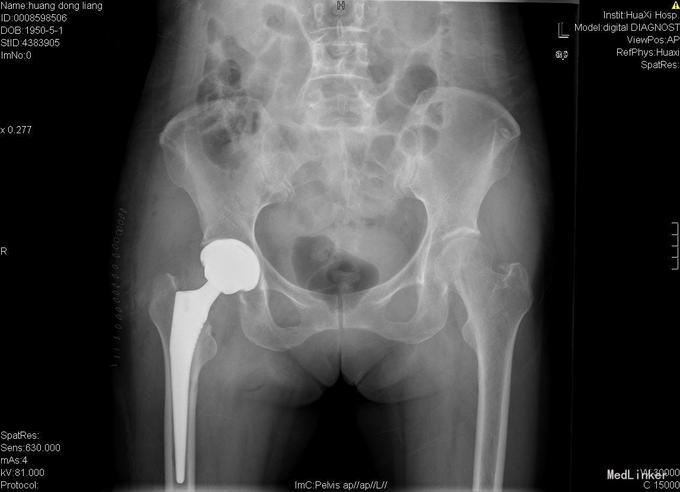

入院诊断:右股骨颈骨折 诊疗计划:择期手术治疗,行右侧全髋关节置换。

骨质疏松性股骨颈骨折患者选用不同治疗方法对预后有着较大的影响,其治疗方案必须考虑骨折部位、类型、移位程度、患者年龄、受伤时间与伤前健康状况等综合因素。股骨颈骨折分型尤为重要,其目的是为了估计预后并指导正确选择治疗方法。